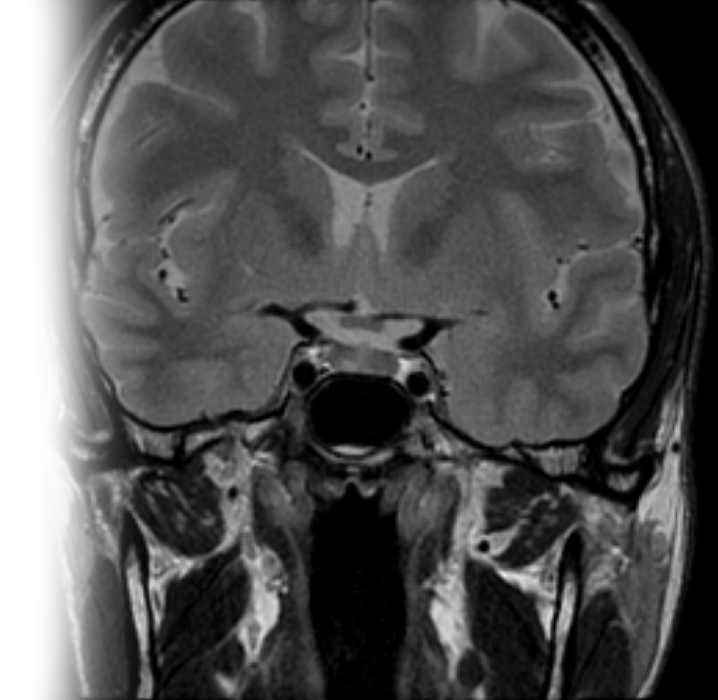

МРТ гипофиза

Магнитно-резонансная томография гипофиза – важный метод исследования, который позволяет оценить состояние гипофиза.